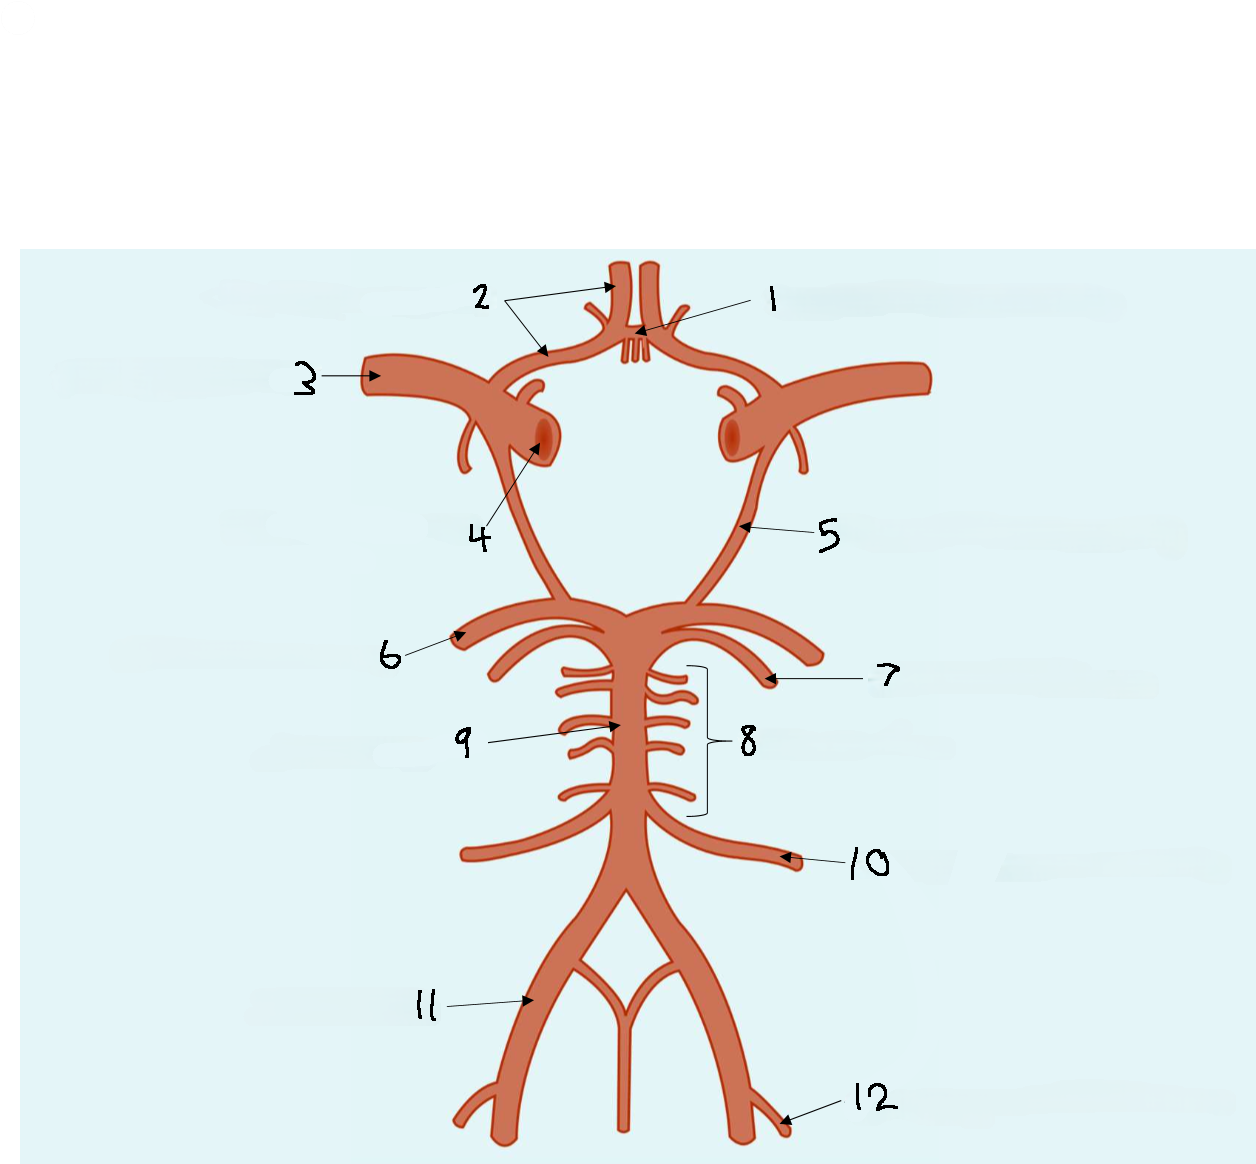

What is 1?

anterior communicating artery

What is 2?

anterior cerebral artery

What is 3?

middle cerebral artery

What is 4?

internal carotid artery

What is 5?

posterior communicating artery

What is 6?

posterior cerebral artery

What is 7?

superior cerebellar artery

What is 8?

pontine arteries

What is 9?

basilar artery

What is 10?

anterior inferior cerebellar artery

What is 11?

vertebral artery

What is 12?

posterior inferior cerebellar artery